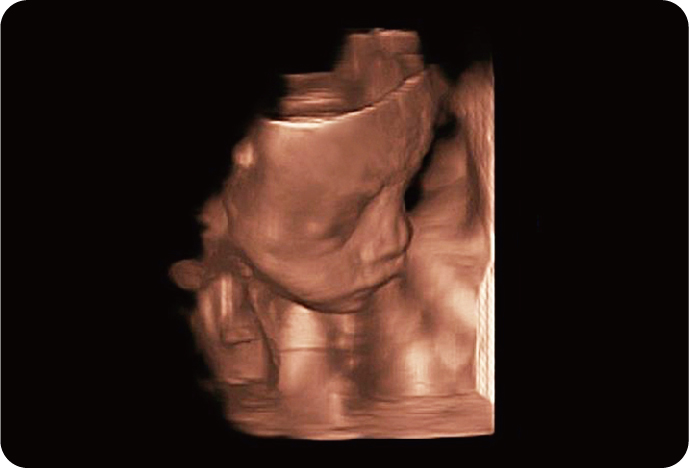

4D Объемный